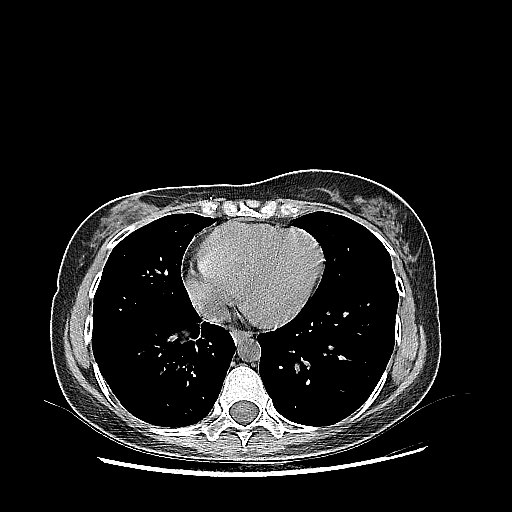

Image Grid

4Γ—3 grid: Rows show different image types (Original NATIVE, Reconstructed NATIVE, Original VENOUS, Generated VENOUS), Columns show windowing techniques (No Window, Lung Window, Mediastinum Window)

Reconstructed NATIVE CT scan (cycle consistency)

Full window (WL 1023.5, WW 4095 β†’ Low βˆ’1024, High +3071)